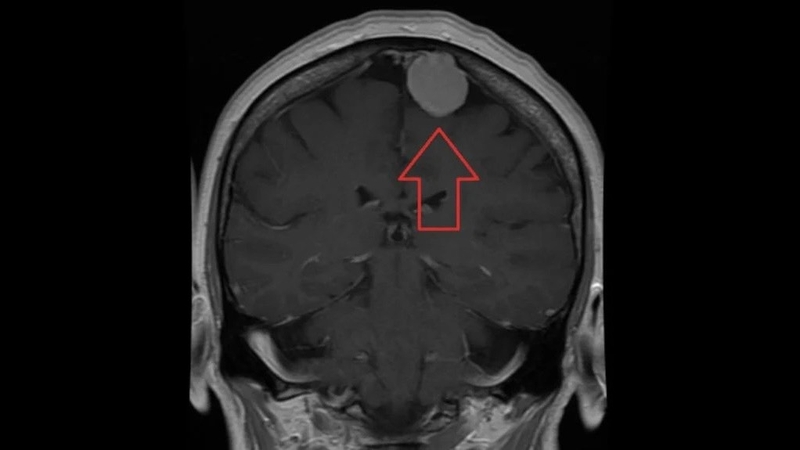

Meningioma là gì?

Meningioma là một loại khối u phát triển từ màng não, lớp mô mỏng bao bọc và bảo vệ não, tủy sống. Hầu hết Meningioma lành tính (không phải ung thư), nhưng một số ít trường hợp có thể ác tính.

Meningioma là khối u não phổ biến nhất, chiếm khoảng 30% tổng số trường hợp u não nguyên phát. Bệnh thường gặp ở người trưởng thành từ 30 đến 50 tuổi và phụ nữ có nguy cơ mắc bệnh cao hơn nam giới.

• Chụp cộng hưởng từ (MRI): MRI sử dụng từ trường, sóng vô tuyến để tạo ra hình ảnh chi tiết nhất về não và khối u, giúp xác định chính xác vị trí, kích thước, cấu trúc, mức độ xâm lấn của Meningioma.